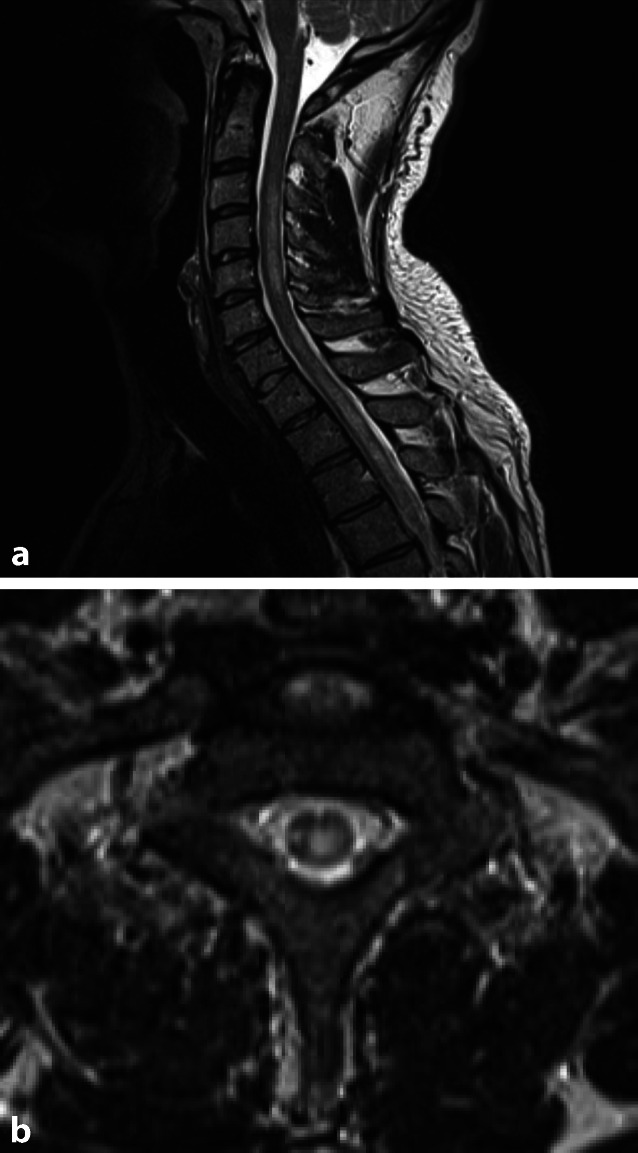

Neuromyelitis-optica-Spektrum-Erkrankungen

Während die MS ihren Inzidenzhöhenpunkt um das 29. Lebensjahr hat, ist dieser bei der Neuromyelitis-optica-Spektrum-Erkrankung etwa 10 Jahre später. Es handelt sich um eine monophasische oder schubförmige demyelinisierende entzündliche Erkrankung des ZNS, wobei vorwiegend die Astrozyten betroffen sind. Früher ging man davon aus, dass die Läsionen nur im Myelon und in den Nervi optici, zu finden sind. Durch verbesserte Diagnostik konnten inzwischen auch weitere zerebrale Läsionen nachgewiesen werden. Typischerweise finden sich im Serum Aquaporin-4-Antikörper (AQP4-Ak). Deren Antigene sind zusätzlich auch am Hypothalamus und an der periependymalen Region lokalisiert, v. a. um das Aquädukt und am 3. und 4. Ventrikel [11], weswegen häufig eine Verwechslung mit der MS auftritt. Dass es sich hier nicht um eine Rose handelt, der man einen anderen Namen gibt, zeigt sich am Versagen der typischen MS-Therapeutika, welche teilweise den Krankheitsverlauf verschlimmern können [4]. Der Druck auf den Neuroradiologen ist hier umso höher, da ein Teil der Patienten negativ für AQP4‑A ist.

Meist sind die Demyelinisierungsherde länger als 2 Wirbelkörper und im Gegensatz zur MS unifokal. Interessanterweise korreliert der Aquaporin-4-Antikörper-Spiegel mit der Länge der Läsionen [12]. Die bevorzugte Lokalisation ist zervikal, teilweise reichen sie bis in das thorakale Myelon und in die Medulla oblongata. Ähnlich der multiplen Sklerose kann es zu einer (ringförmigen) Kontrastmittelaufnahme und fokaler Schwellung kommen. Da vorwiegend die graue Substanz betroffen, ist die Lokalisation zentral und meist symmetrisch (Abb. 2a, b). Wenn sich in der T1w-Hypointensitäten in den Herden zeigen, reflektiert dies den größeren Gewebeschaden, und ist typisch für die NMOSD.